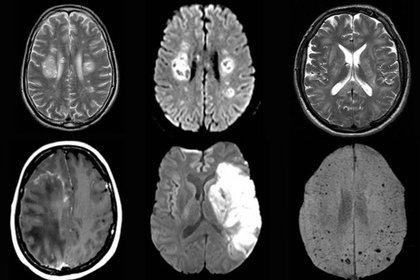

Cambios cerebrales en la resonancia magnética  a tres meses en  pacientes con COVID-19

Unos 60 pacientes recuperados y 39 controles fueron sometidos a resonancia magnética cerebral. La cohorte COVID-19 mostró una amplia gama de diferencias con respecto a los controles, incluidos volúmenes de materia gris bilaterales significativamente más altos en las cortezas olfativas y los hipocampos. Algunas de estas diferencias se asociaron con síntomas persistentes como pérdida de memoria y olfato. Los investigadores señalan que los hallazgos indican "el potencial de neuroinvasión del SARS-CoV-2 ... incluso si los pacientes se recuperan bien de la condición de neumonía, los cambios neurológicos pueden causar una gran carga". EClinicalMedicine, 3 de agosto de 2020